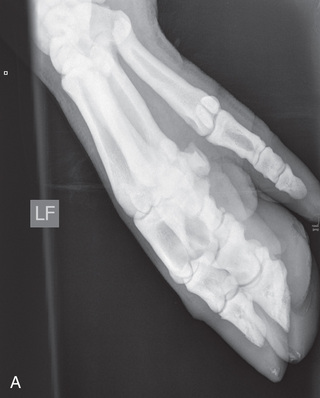

Digit/foot: P-III (distal phalanx, coffin bone) P-II (middle phalanx) P-I (proximal phalanx-pastern) Proximal interphalangeal joint (pastern joint) joint | DP (Standard) (Fig. 24.62B,C) | Dorsal 45-degree proximal–palmarodistal (D45Pr-PaDi) | Foot slightly forward on image receptor. | Perpendicular to foot axis at MSP (midsagittal plane) at area of interest with beam angled ~45 degrees to ground |

| Lateral (Standard) (Fig. 24.62D) | Lateromedial | On a block to elevate limb for P-III; resting on ground for other views. | 90 degrees lateral to MSP, parallel to ground on area of interest: coronary band for PIII | |

DLPMO (Optional) | Dorsoproximal 45-degree lateral–palmarodistomedial oblique (DPr45L-PaDiMO)/(DPr45M-PDiLO) | As for the lateral view for P-III. | 45 degrees to ground on the area of interest | |

| DMPLO (Optional) | Dorsoproximal 45-degree medial–palmarodistolateral oblique (DPr45M-PaDiLO) (DMPLO) | As for the DP view for P-II and P-I | 45 degrees lateral to MSP directed either laterally (DLPMO) or medially (DMPLO) | |